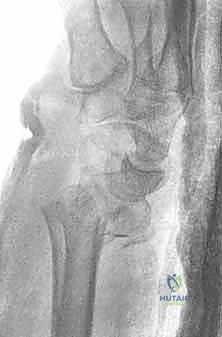

1. الأشعة السينية (X-rays): بوضعيات متعددة (أمامية خلفية، وجانبية دقيقة). الوضعية الجانبية الحقيقية (True Lateral) حاسمة لاكتشاف أي خلع جزئي في المفصل (DRUJ).

2. الأشعة المقطعية ثلاثية الأبعاد (3D CT Scan): تُستخدم في الكسور المفتتة أو كسور رأس الزند المفصلية المعقدة، حيث تعطي خريطة دقيقة للجراح قبل الدخول لغرفة العمليات.